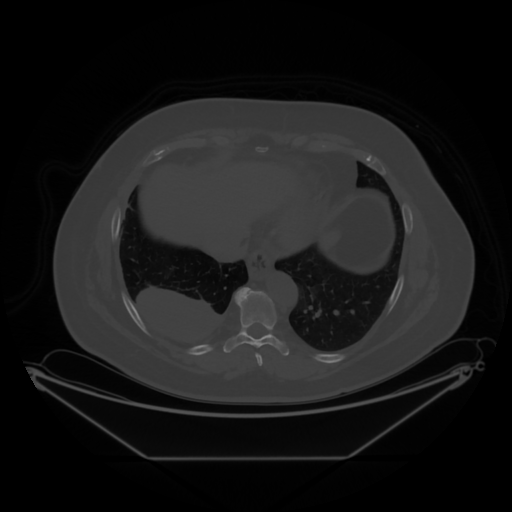

Original NATIVE CT scan (input)

Full window (WL 1023.5, WW 4095 β†’ Low βˆ’1024, High +3071)

Lung window (WL -600, WW 1500 β†’ Low βˆ’1350, High +150)

Mediastinum window (WL 40, WW 400 β†’ Low βˆ’160, High +240)